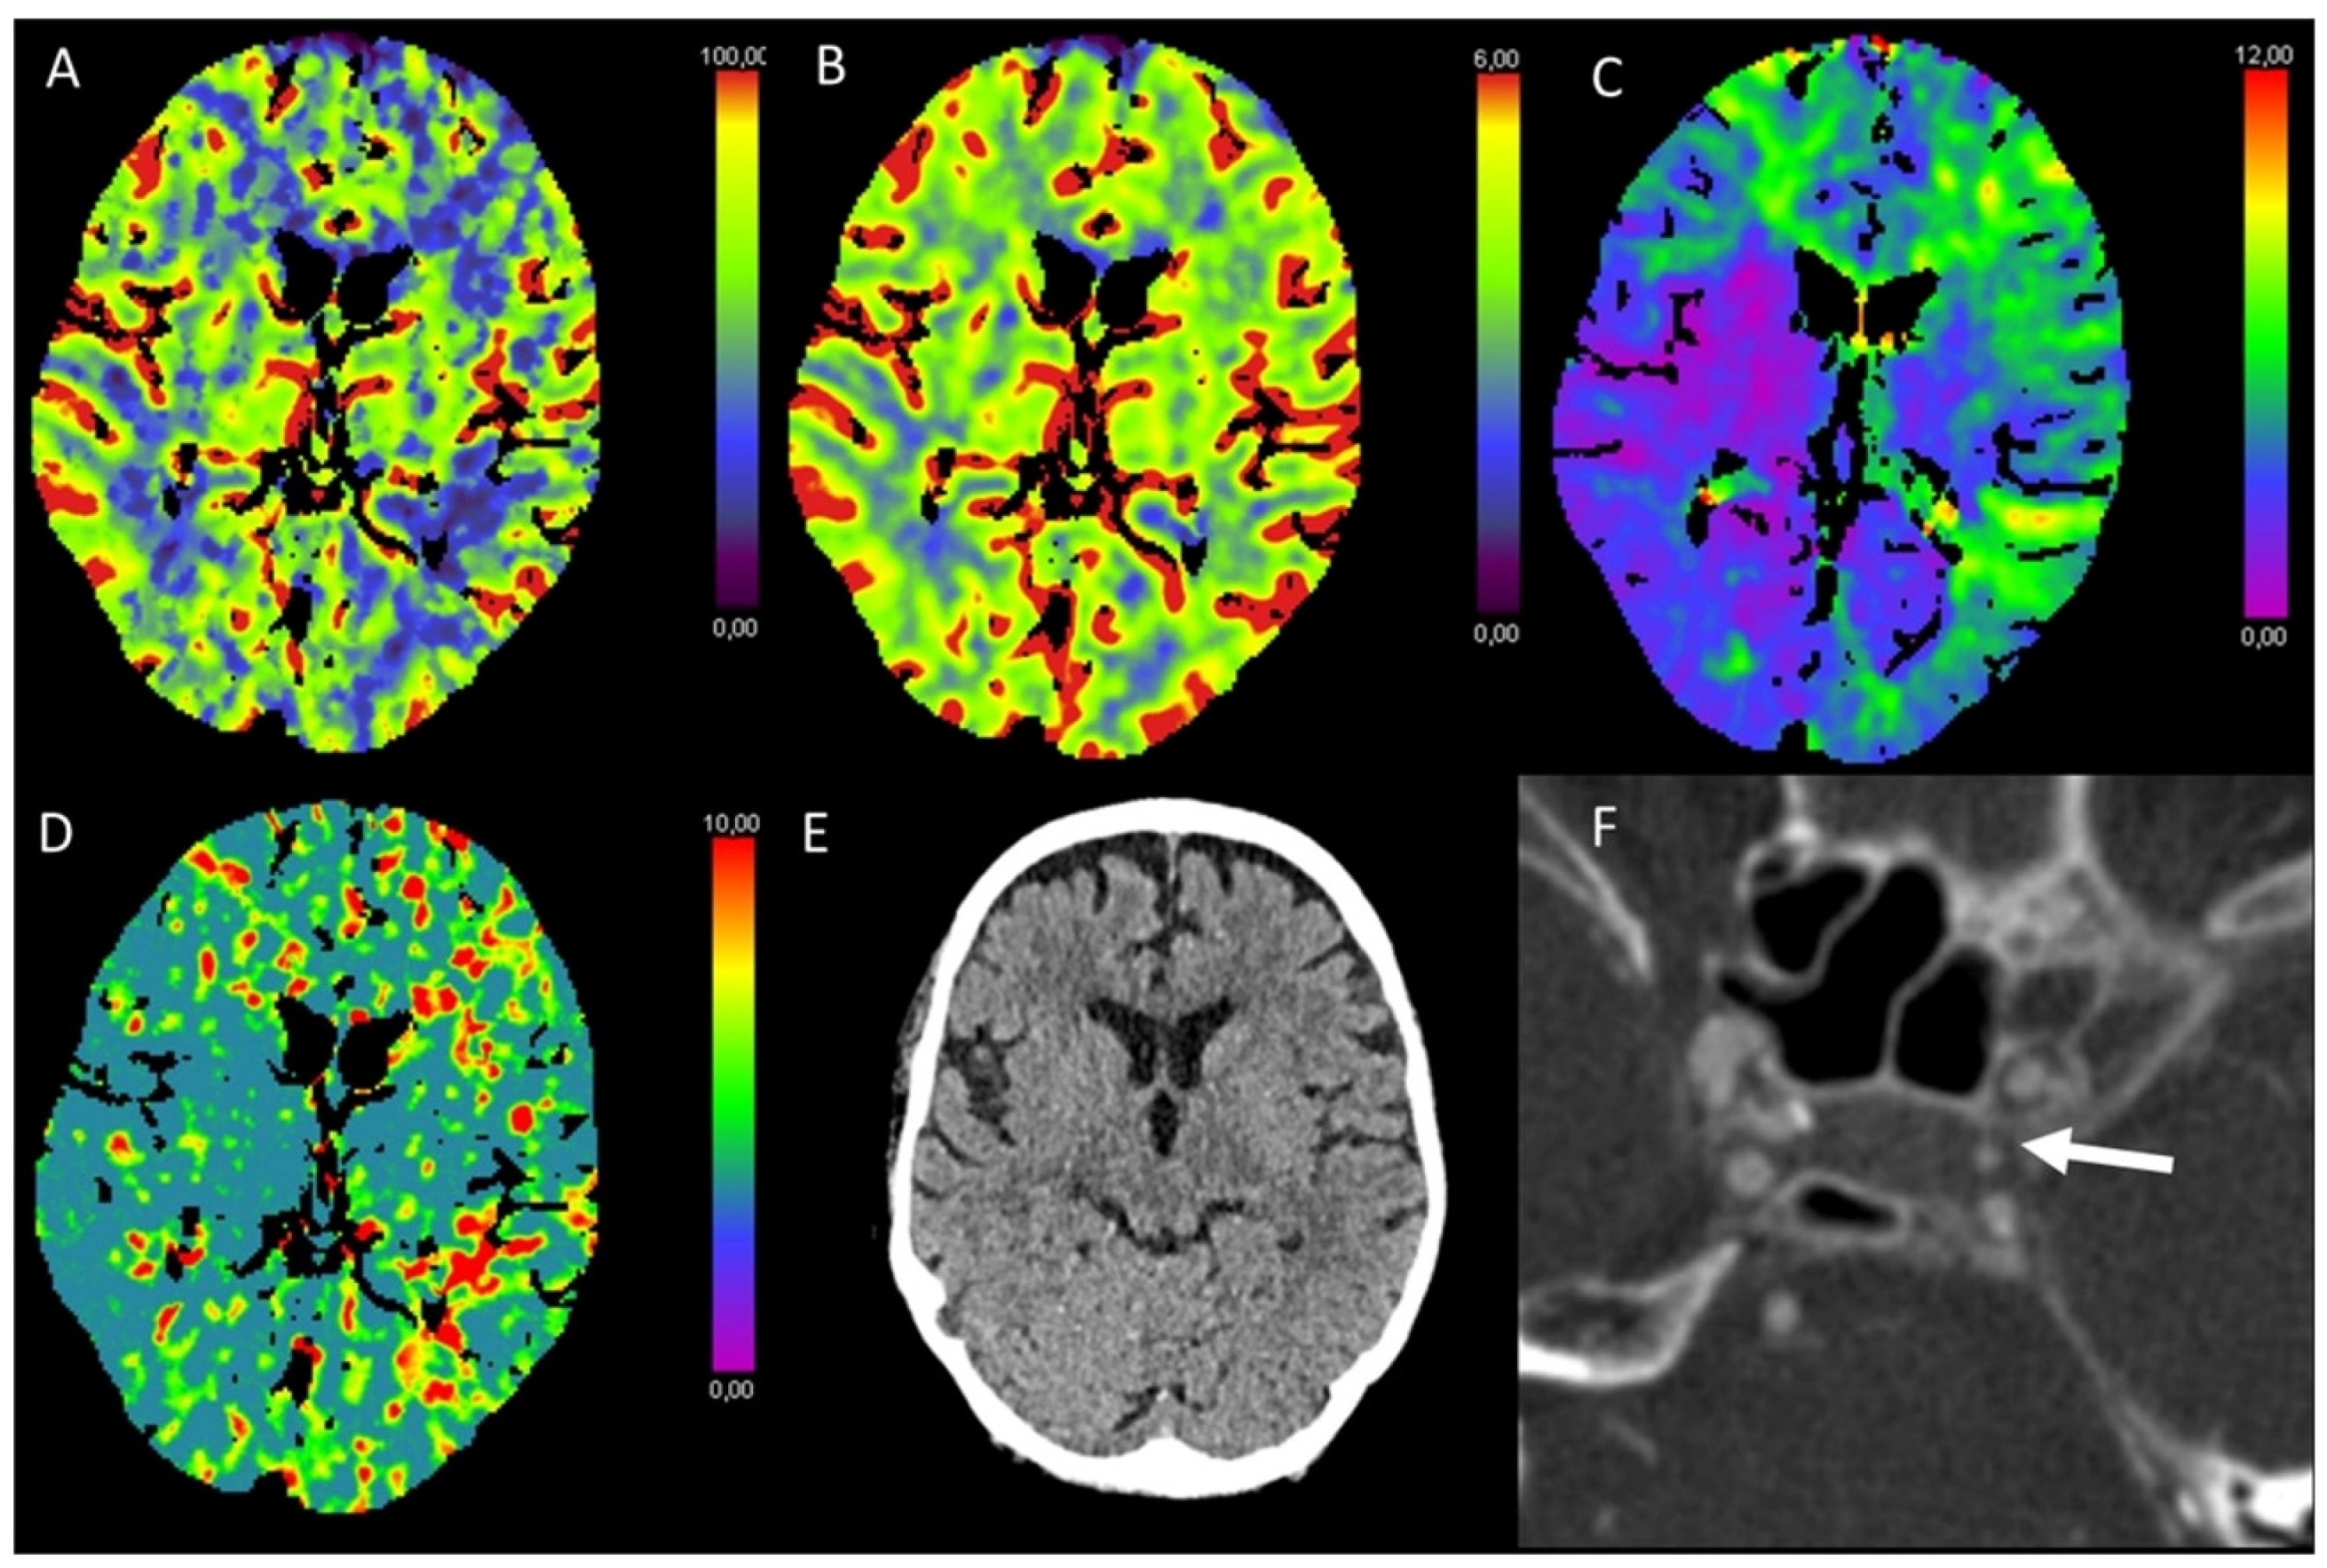

3.5. Hypotensive Cerebral Infarction (HCI) with Watershed Infarcts/Border Zones